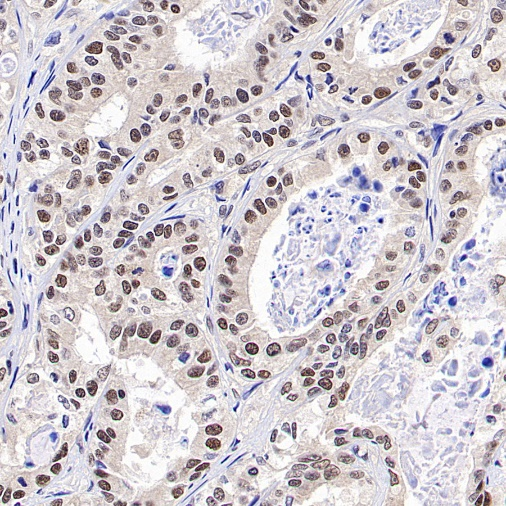

Positive staining

IHC shows positive staining in paraffin-embedded human endometrial cancer

Negative control

IHC shows negative staining in paraffin-embedded human skeletal muscle